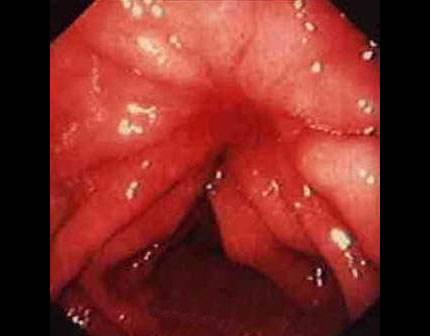

摘要:痔瘡癌變是嚴(yán)重的健康問題,其前兆包括便血、疼痛、肛門不適、排便習(xí)慣改變等10個(gè)跡象。了解并識別這些前兆的重要性在于早期發(fā)現(xiàn)、診斷和治療,以提高治愈率和生存率。對于痔瘡患者,密切觀察并及時(shí)就診是預(yù)防癌變的關(guān)鍵。

痔瘡癌變的10個(gè)前兆

1、痔瘡疼痛加劇:痔瘡患者如感覺疼痛逐漸加劇,可能是癌變的一個(gè)信號。

2、痔瘡出血:長期痔瘡出血,尤其是出現(xiàn)持續(xù)性出血時(shí),應(yīng)警惕癌變的可能。

3、痔瘡體積變化:如痔瘡體積在短時(shí)間內(nèi)迅速增大,可能是癌變的征兆。

4、排便習(xí)慣改變:如排便頻率增加或減少,以及出現(xiàn)便秘與腹瀉交替的情況,可能與痔瘡癌變有關(guān)。

5、肛門不適:出現(xiàn)肛門墜脹、異物感等癥狀時(shí),應(yīng)考慮痔瘡癌變的可能性。

6、消瘦和乏力:如體重迅速下降、乏力等全身癥狀出現(xiàn)時(shí),可能是痔瘡癌變的警示信號。

7、淋巴結(jié)腫大:如出現(xiàn)腹股溝或盆腔淋巴結(jié)腫大,可能與痔瘡癌變有關(guān)。

8、食欲減退:長期食欲減退,尤其是伴有上述癥狀時(shí),應(yīng)警惕痔瘡癌變。

9、肛周瘙癢:肛周瘙癢可能是痔瘡炎癥的表現(xiàn),長期不緩解可能發(fā)展為癌變。

10、便血顏色變化:如便血顏色由鮮紅色變?yōu)榘导t色或混合有黏液,應(yīng)引起重視。